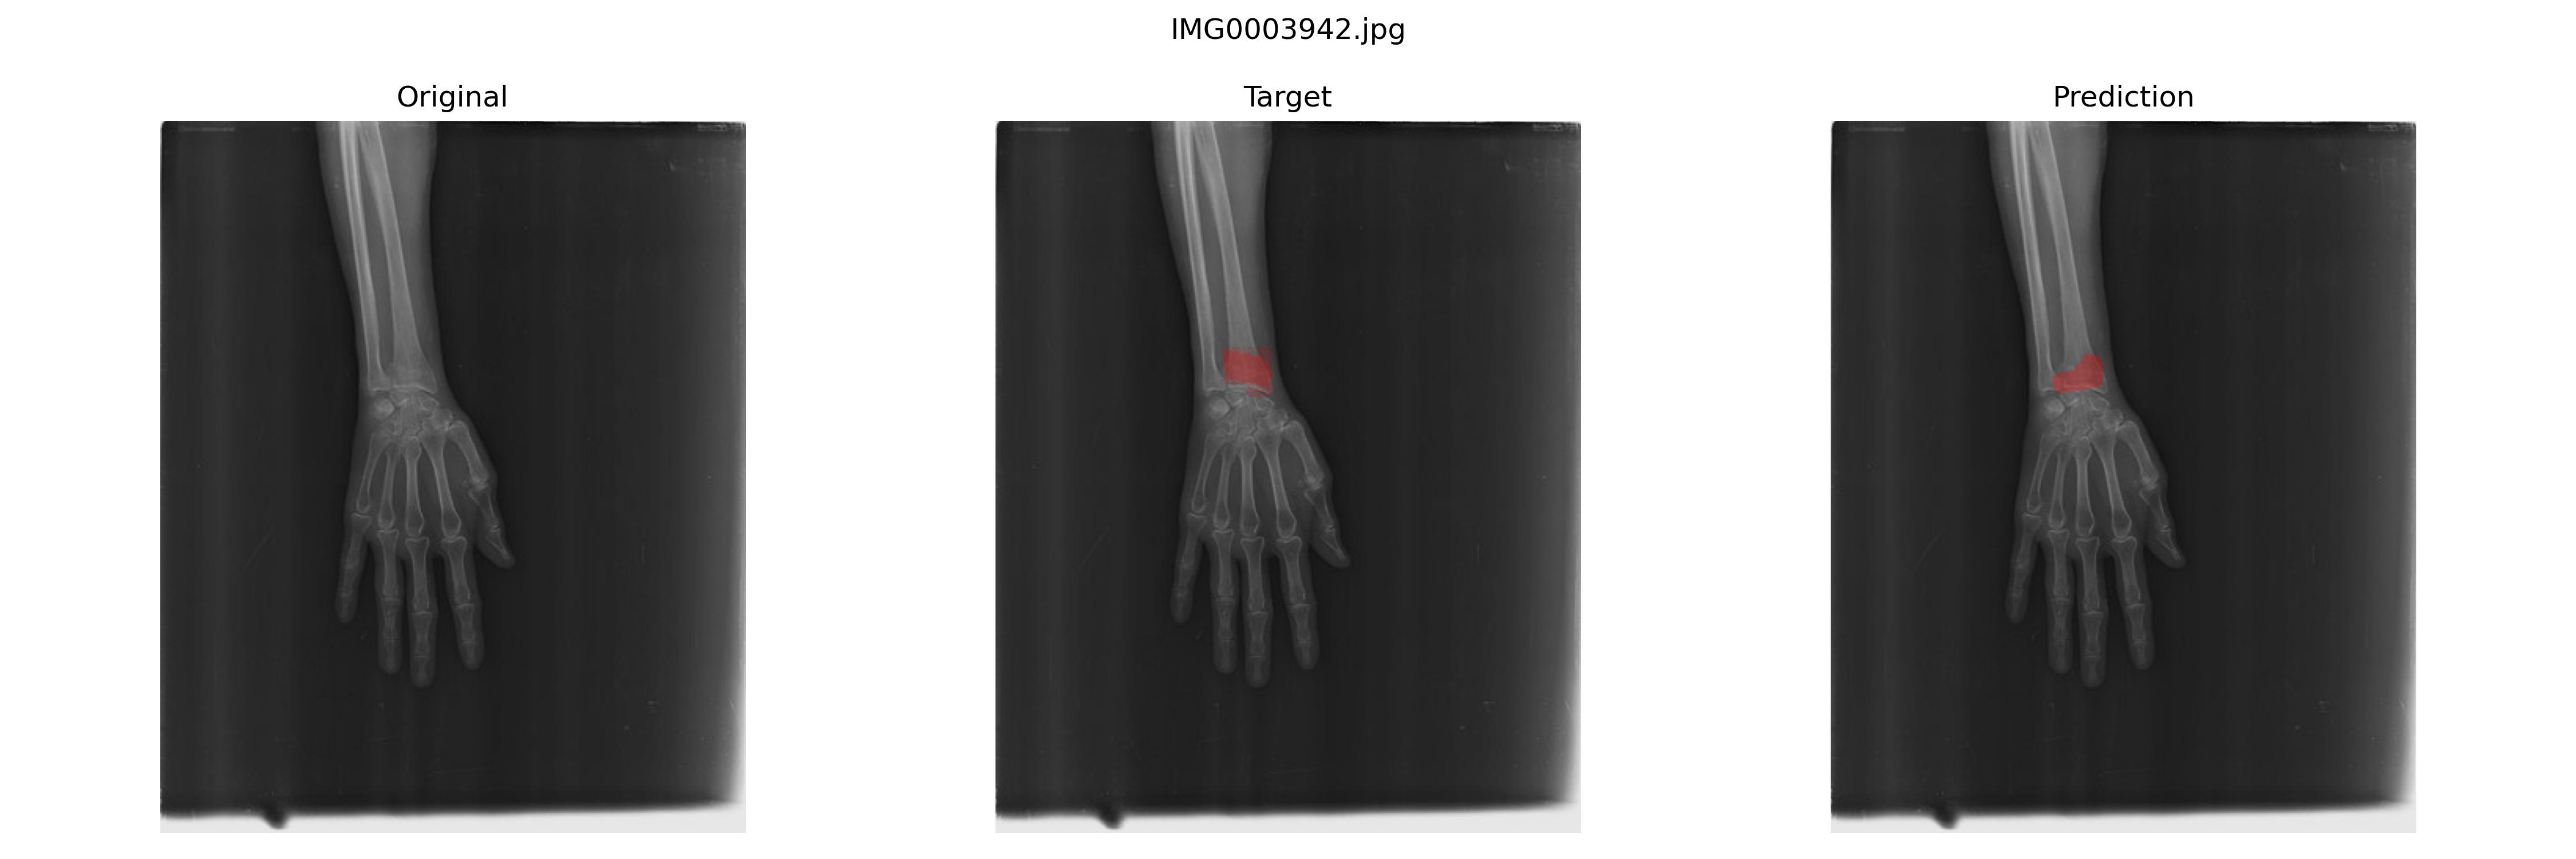

结果预览

我感觉甚至可以说在一些地方,模型分割得比Ground Truth要好一些。